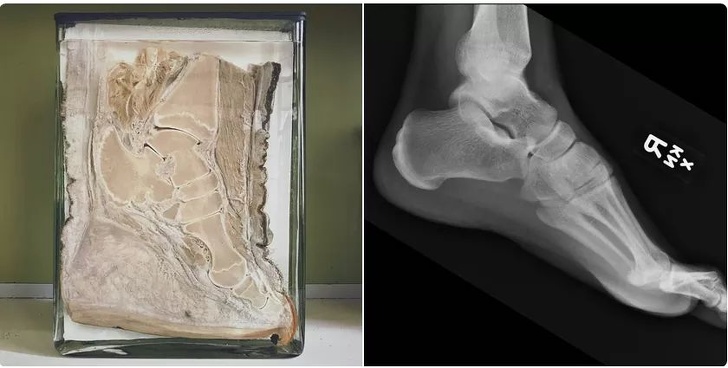

11. Elephant vs human foot

Illustration de l'article : 15 fascinating photos that say a lot about the human body

© reddit